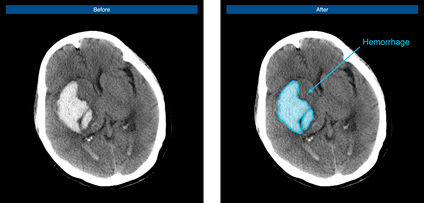

腦出血病例示意圖

腦血管疾病領(lǐng)域作為推想醫(yī)療早期布局的重要疾病領(lǐng)域之一,在近年的北美放射協(xié)會年會(RSNA)上,公司便展示了首款腦卒中AI在研產(chǎn)品,通過不斷研發(fā)和快速迭代“進(jìn)化”,該產(chǎn)品已可快速判別是否存在出血、高效標(biāo)注出血病變、準(zhǔn)確定位和勾畫出血區(qū)域、快速自動(dòng)計(jì)算出血體積,從而提升醫(yī)生的診斷速度,完善院端急救場景的智能分診和流程管理,并最終為腦卒中患者贏得救治黃金期。